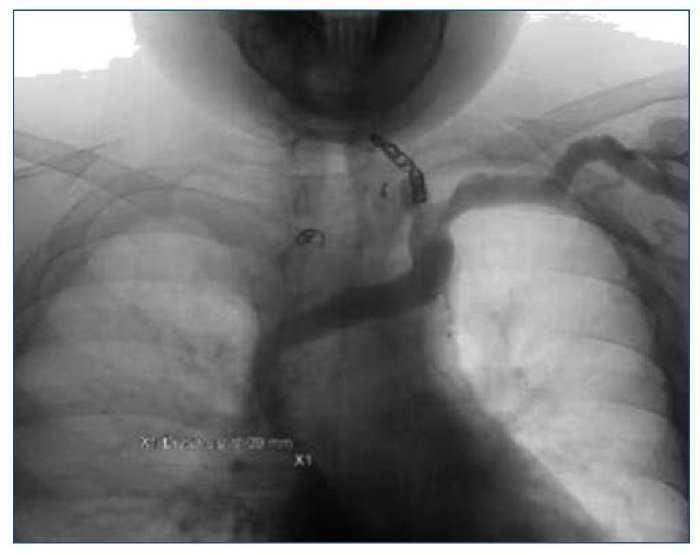

Dos meses más tarde, una nueva EDA observa cordones varicosos en tercio medio, estables. En ese tiempo se realiza flebografía, observando oclusión de la VCS con colateralidad a través del sistema ácigos (figura 1).

Figura 1. Cavografía con oclusión de la vena cava superior y colateralidad a través fundamentalmente del sistema ácigos.